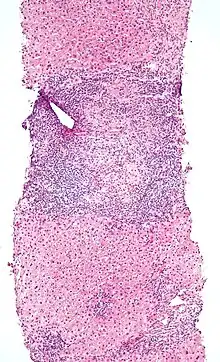

Low-magnification micrograph of PBC, H&E stain

On microscopic examination of liver biopsy specimens, PBC is characterized by chronic, nonsuppurative inflammation, which surrounds and destroys interlobular and septal bile ducts. These histopathologic findings in primary biliary cholangitis include:[32]

- Inflammation of the bile ducts, characterized by intraepithelial lymphocytes

- Periductal epithelioid granulomas.

- Proliferation of bile ductules

- Fibrosis (scarring)

The Ludwig and Scheuer scoring systems have historically been used to stratify four stages of PBC, with stage 4 indicating the presence of cirrhosis. In the new system of Nakanuma, the stage of disease is based on fibrosis, bile duct loss, and features of cholestasis, i.e. deposition of orcein-positive granules, whereas the grade of necroinflammatory activity is based on cholangitis and interface hepatitis. The accumulation of orcein-positive granules occurs evenly across the PBC liver, which means that staging using the Nakanuma system is more reliable regarding sampling variability.